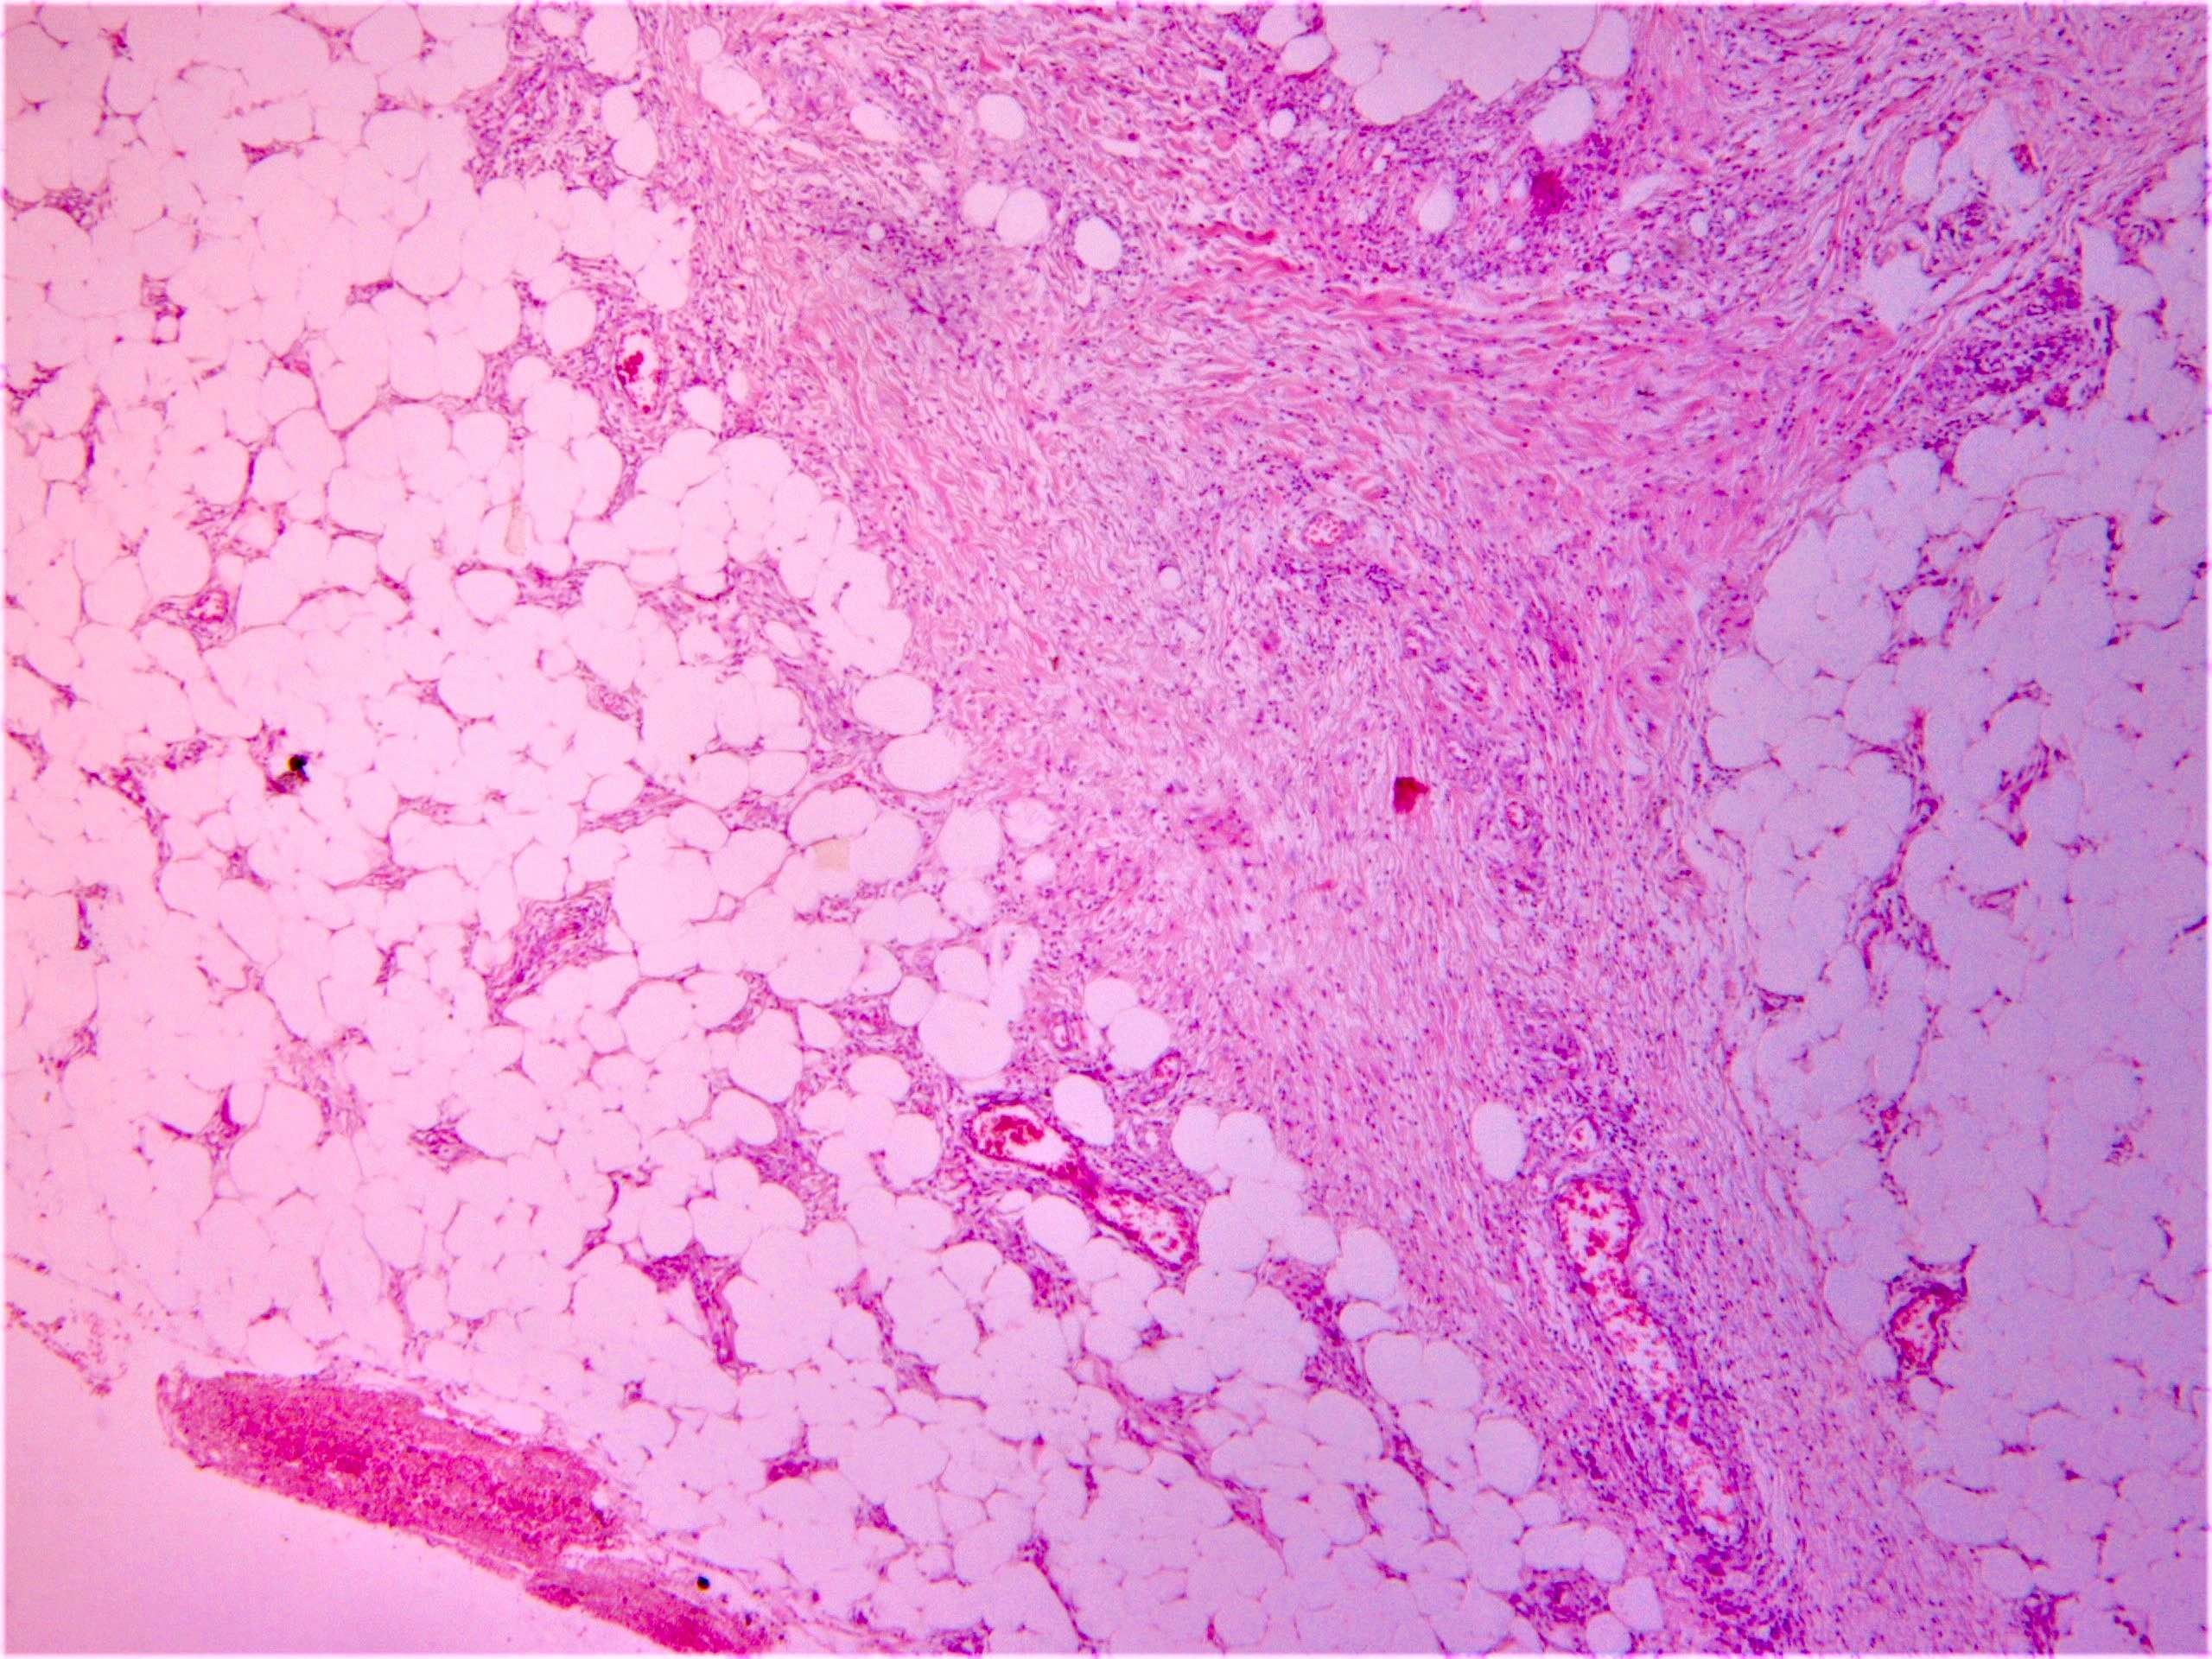

Microscopic (histologic) description

- Erythema nodosum-like lesions: septal panniculitis; vasculitis (lymphocytic or neutrophilic) and necrobiosis may be found

Microscopic (histologic) images

Sample pathology report

- Right leg, erythematous subcutaneous nodule, incisional biopsy:

- Erythema nodosum-like lesion (given the history, compatible with Behçet disease) (see comment)

- Comment: Septal panniculitis with unremarkable epidermis. Dermis shows moderate perivascular lymphocytic infiltrate. The subcutaneous fat demonstrates widening of the fibrous septa with edema and infiltration of lymphocytes and histiocytes. Spillover of infiltrate to the adjacent fat lobules is present. Small focus of lymphocytic vasculitis is noted.